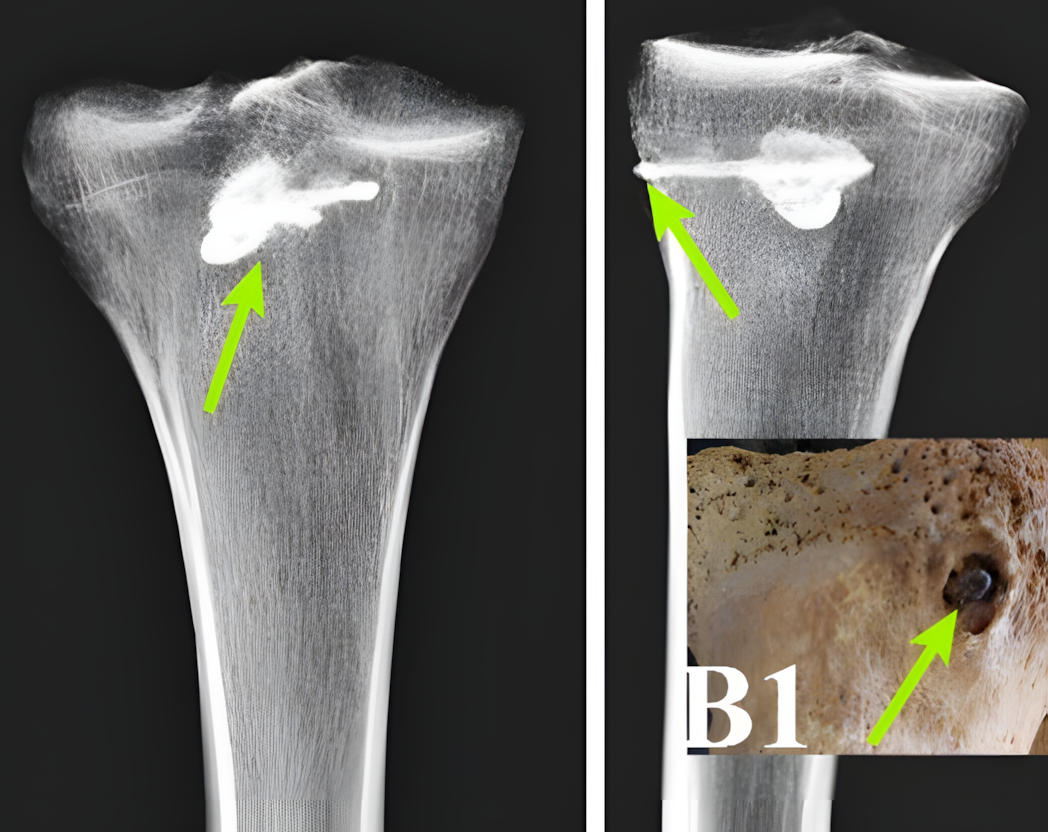

연구진은 X선 형광 분석, 양자계 분석, CT 스캔 등 최첨단 기술을 활용하여 전사의 오른쪽 정강이뼈에 박힌 금속 물체를 확인했다.

이 물체는 길이 44mm, 너비 15mm의 정교한 삼날 금속 화살촉으로, 알려진 다른 파르티아 무기들과 일치했다.

뼈 분석 결과 박힌 화살촉 주변에서 명확한 치유 흔적이 발견되었다.

이물질 주변에 치밀한 뼈 조직이 형성되기 시작하여 전사가 초기 외상에서 살아남았고 그 후 상당 기간 생존했음을 시사한다.

그러나 관통 부위 바로 밖에서는 감염이나 새로운 뼈 형성의 흔적이 발견되지 않았다.

"뼈 구조는 beam 주변에서 치유 흔적을 보이고 있으며, 상처의 외부 상태는 상당한 시간이 지났고 치유 과정이 진행되었음을 시사한다"고 에그다미 박사는 설명했다.